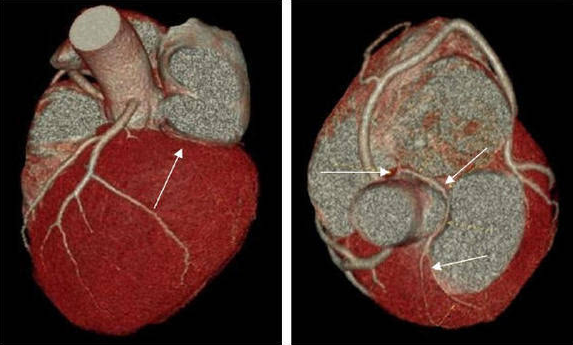

冠状动脉CTA检查是一项用于检查动脉血管是否正常的辅助检查,通过注射造影剂做血管造影可得CT血管造影,用于判断大动脉炎、动脉硬化闭塞症、主动脉瘤及夹层 等病症,用于帮助临床诊断。是冠心病早期筛查的首选,冠脉PCI、搭桥随访观察,冠脉钙化精确测定的最优选择。